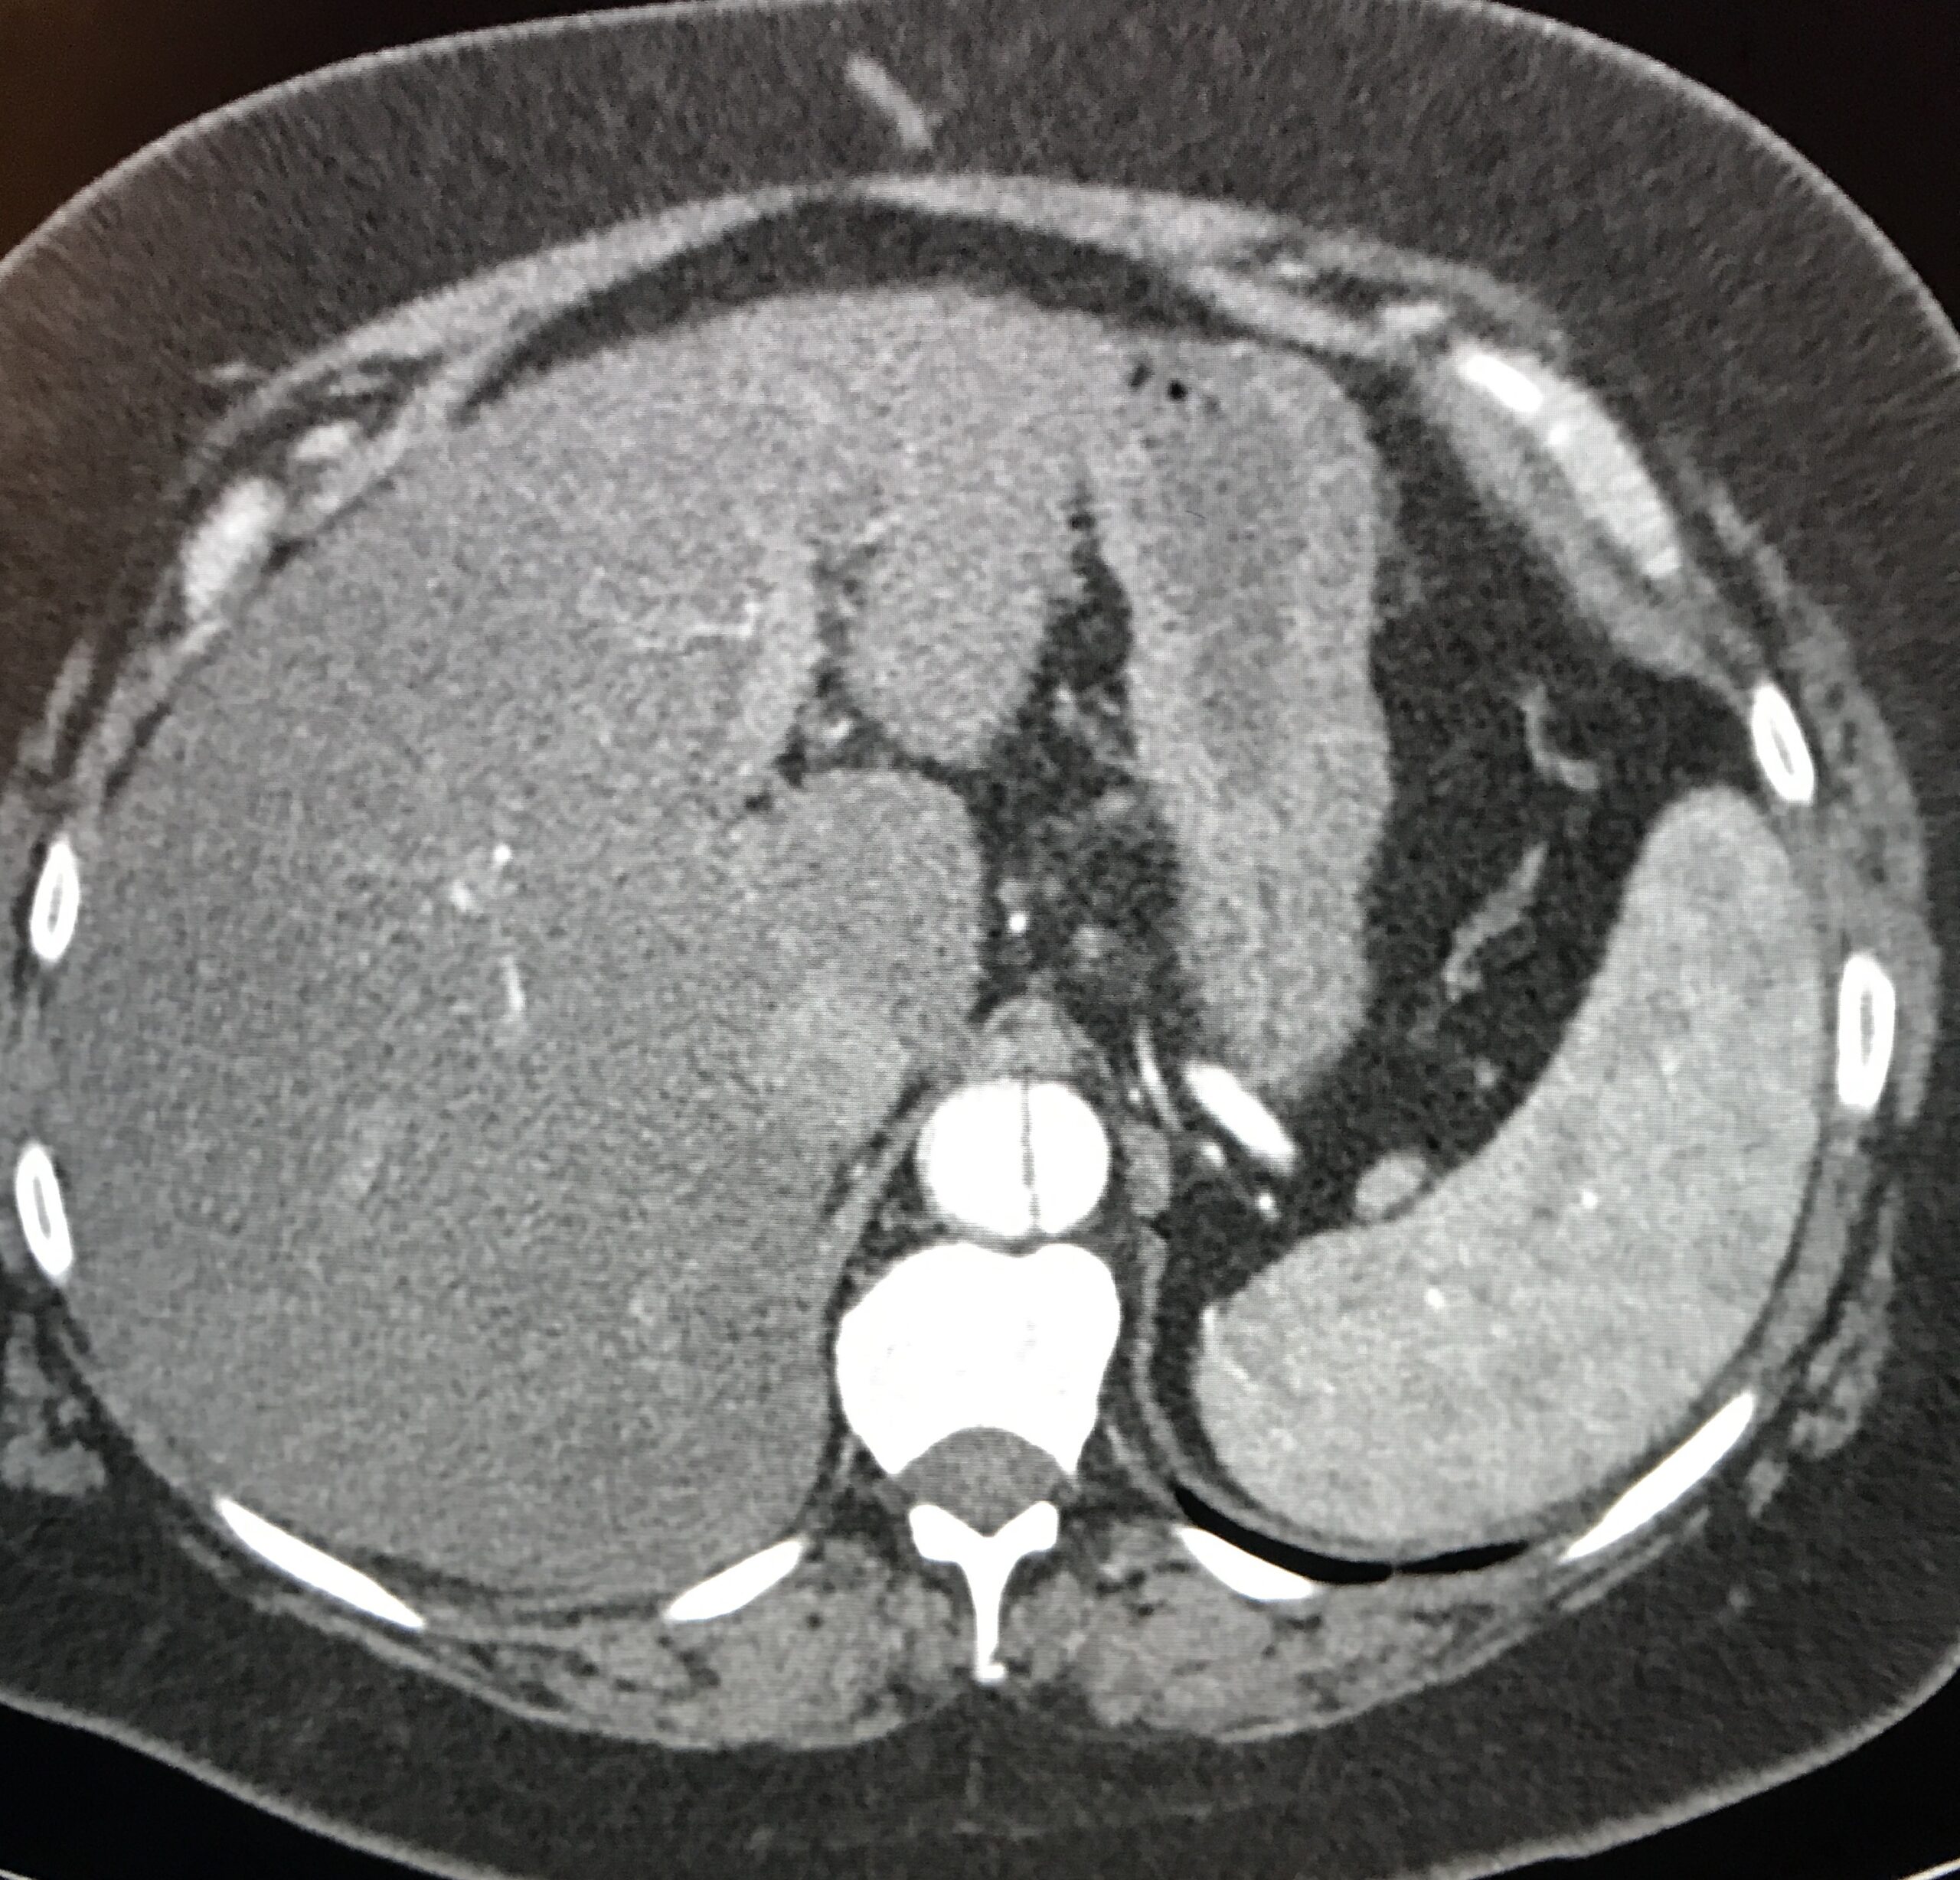

- A CT urogram is obtained and shows:

Image courtesy of Sam Ashoo, MD

Diagnosis: Acute Descending (Type B) Aortic Dissection

- The benefit of contrast: Though CT imaging has come a long way, the identification of vascular abnormalities continues to require the administration of intravenous contrast. As this case highlights, non-contrast imaging of the aorta relies on edema of surrounding structures or aneurysmal dilatation of the aorta to suggest abnormality. In the absence of either of these findings, no further analysis of the aorta can be made. The addition of contrast clearly highlights the intra-vascular space allowing for the correct diagnosis of this life threatening disease.